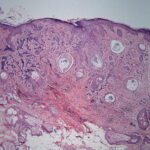

Histopathologic examination reveals a relatively well-circumscribed lesion in the upper two-thirds of the dermis with a focal epidermal connection. It is composed of basaloid aggregations arranged predominantly in columns and cords and admixed with infundibulocystic structures, surrounded by a dense, hypocellular desmoplastic stroma. It may occasionally be difficult to distinguish this entity histologically from malignant desmoplastic lesions such as aggressive growth basal cell carcinoma or MAC. Treatment. Local surgical excision is the preferred treatment